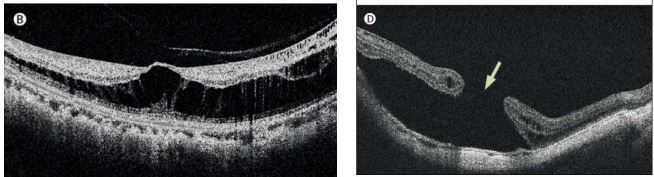

13

Q

What is this?

A

Macular hole

Right is full thickness mac hole